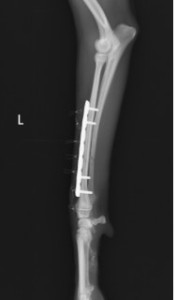

手術前 手術後

ロッキングプレートで整復しました。